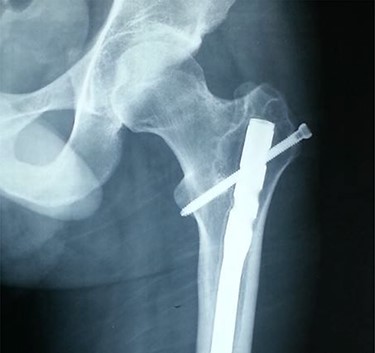

Anteroposterior radiograph showing a buried intramedullary nail.